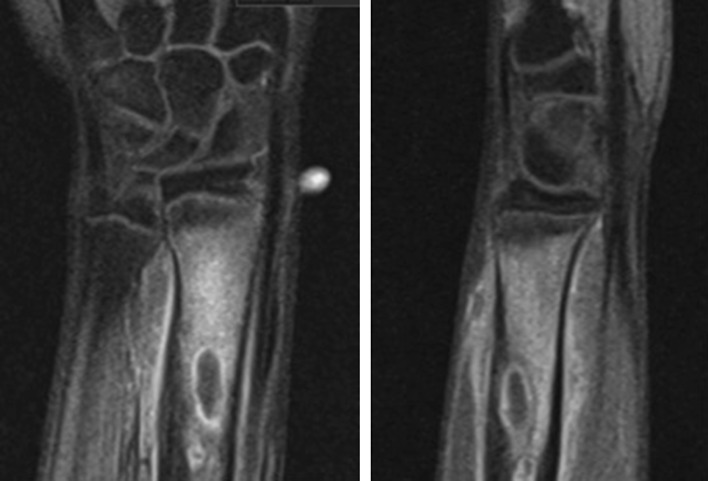

Fig. 3.

MRI scan of the left distal radius showing cystic lesions in the distal radius with surrounding oedema and an area of cortical discontinuity